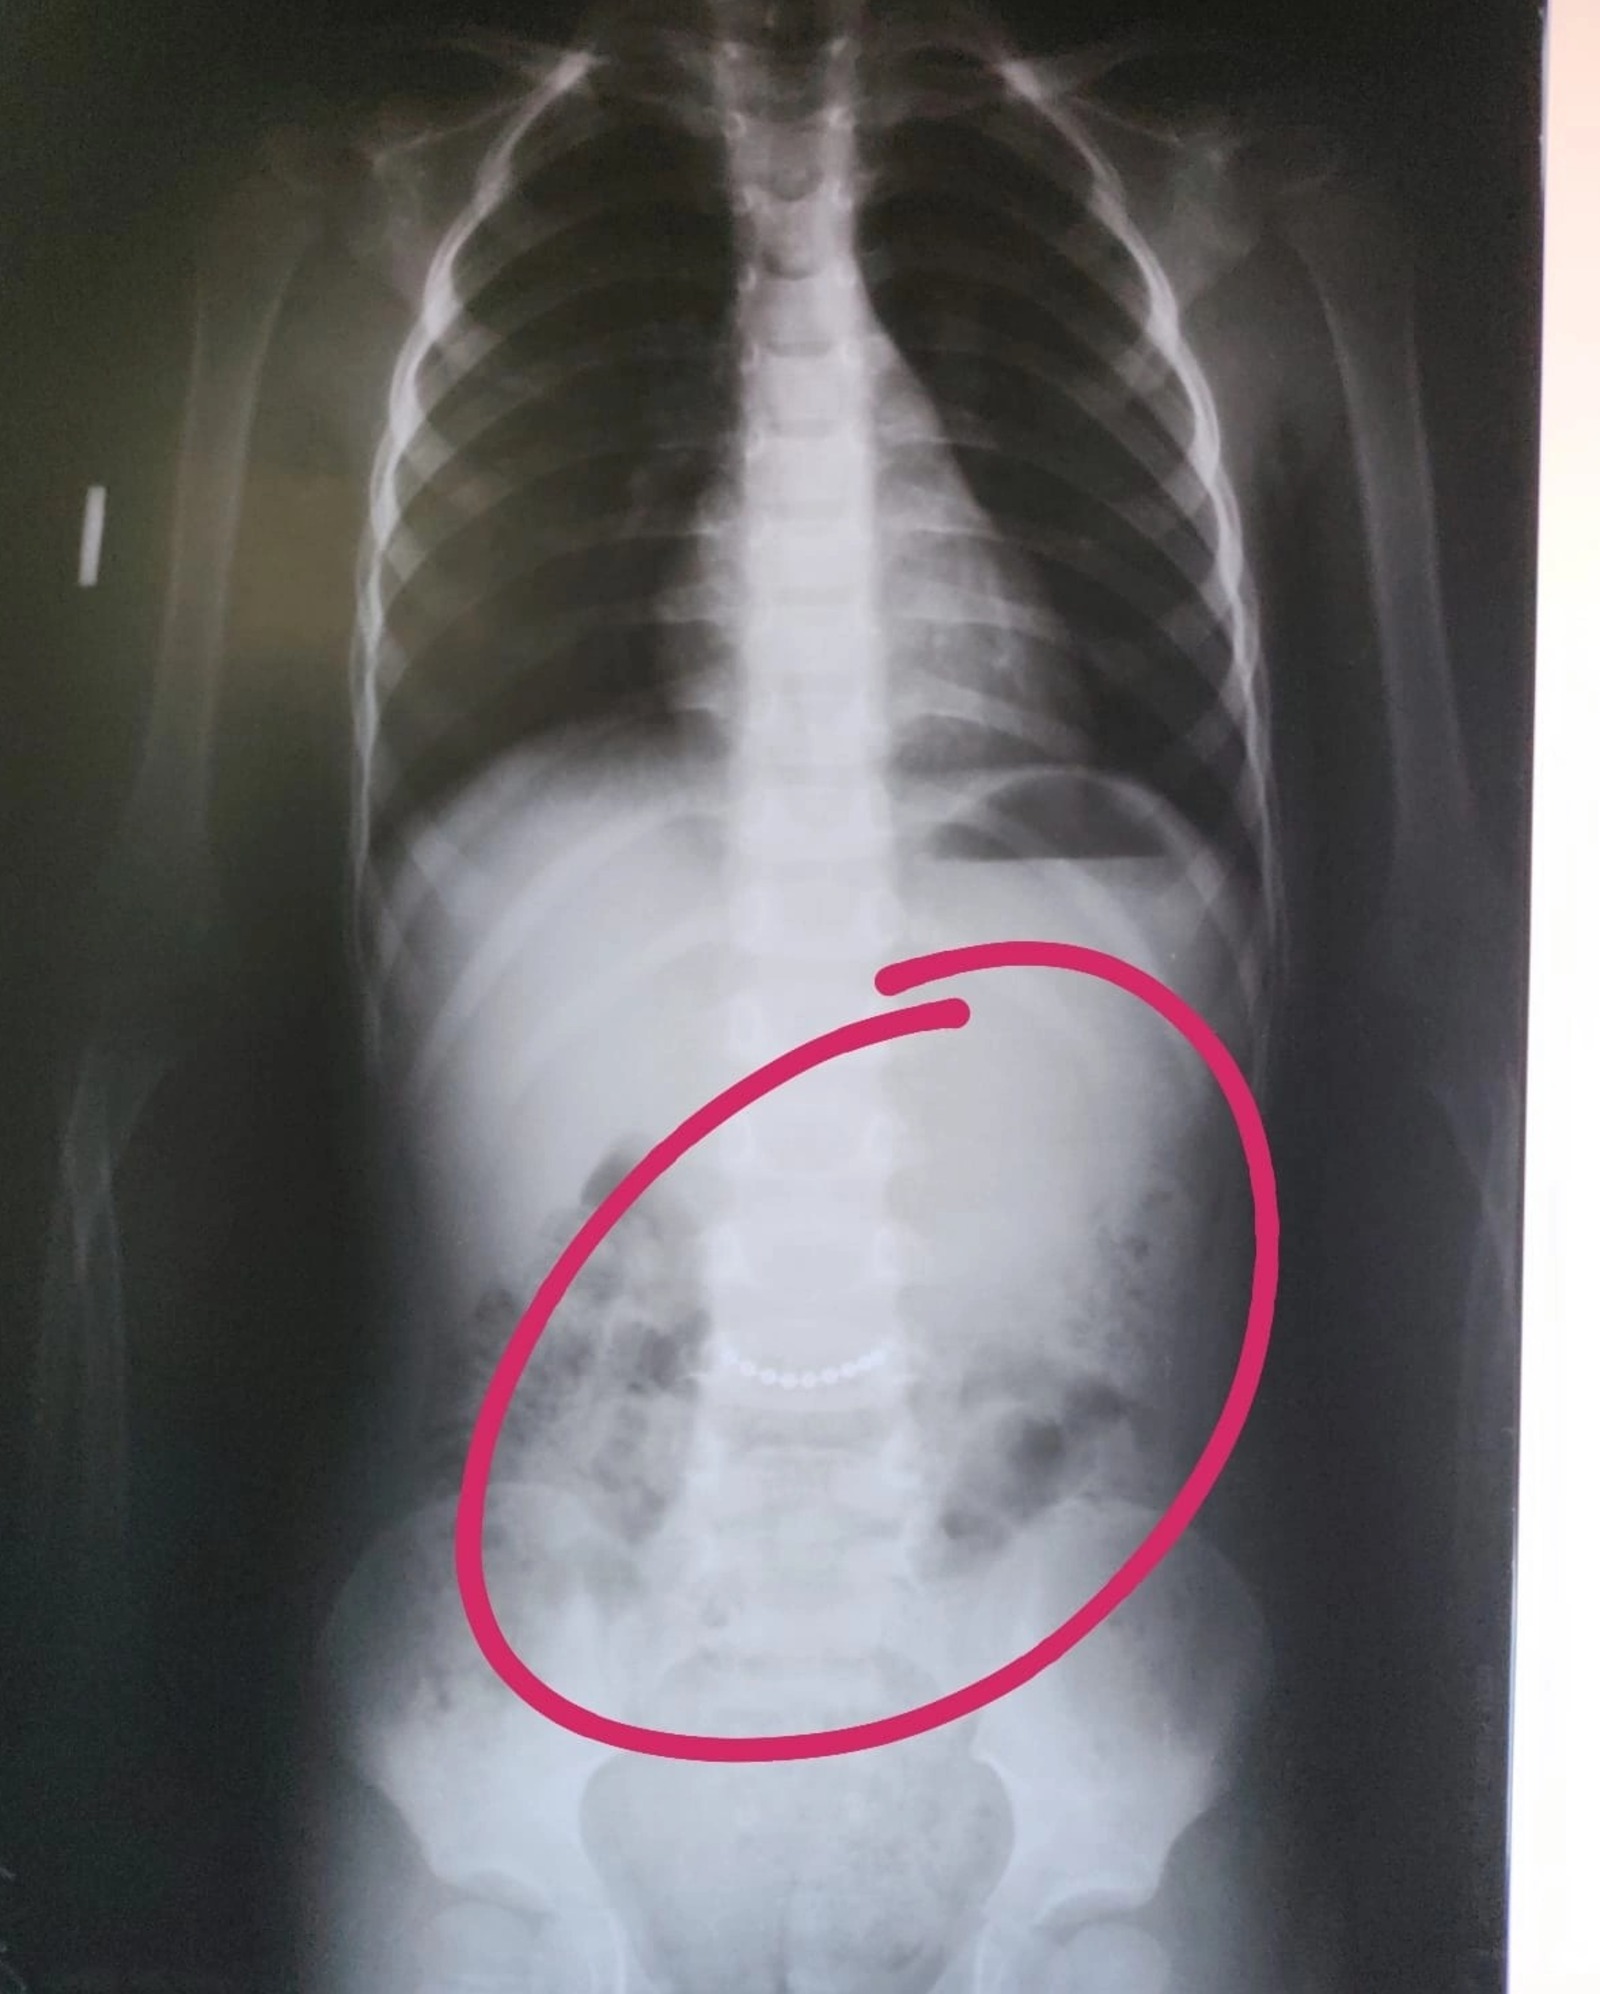

Фото:Раевская ЦРБ В Башкирии медики обнаружили в животе трехлетнего ребенка цепочку.

В Башкирии медики обнаружили в животе трехлетнего ребенка цепочку. Пациент с подозрением на инородное тело в брюшной полости поступил в центральную районную больницу в селе Раевский.

Рентген подтвердил наличие металлического предмета. Как оказалось, это была цепочка. К счастью, она покинула детский организм, не успев нанести серьёзный вред.